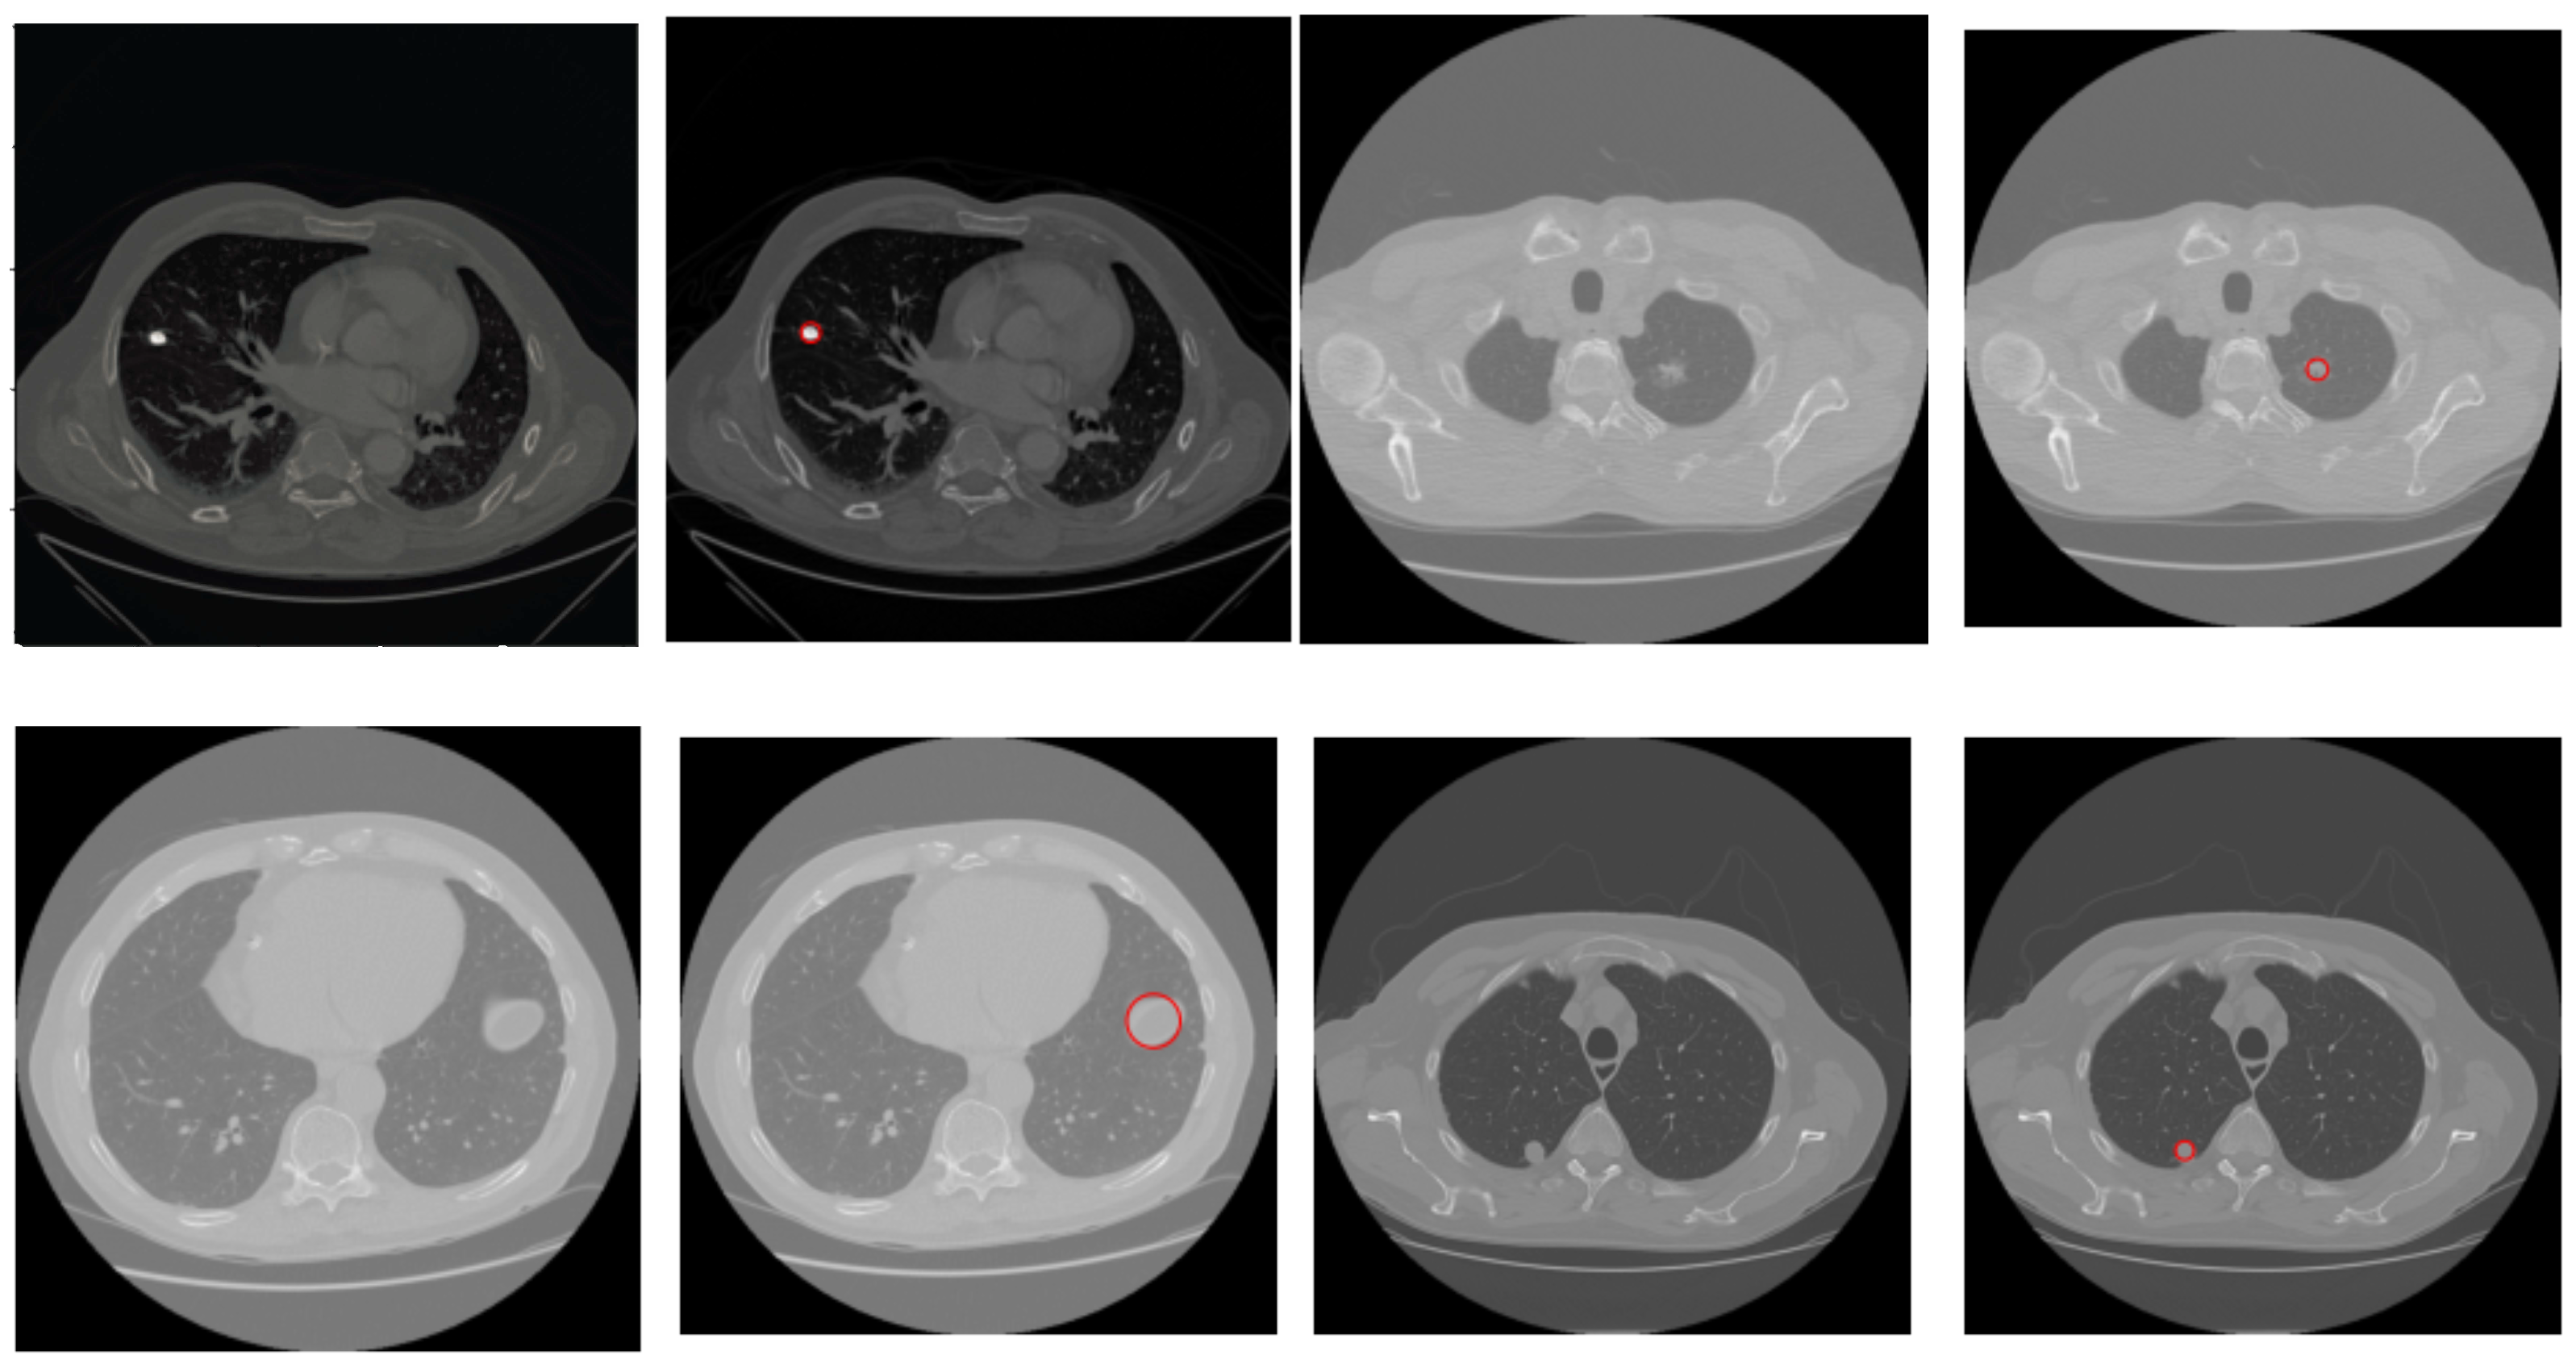

In Figure 10, we present a few results of the proposed algorithm on test images from the LUNA16 dataset. The results and statistics presented in Table 2 show that the proposed method is quite accurate and reliable. Moreover, it works for both lung window scans and mediastinal window scans and achieves better accuracy.

Figure 10.

Results of the proposed algorithm on a few images from the dataset. In each pair, the left is the test image and the right is the image, with the detected nodule highlighted in a red circle.